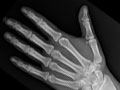

Extremity X-Ray

Test Overview

An extremity X-ray is a picture of your hand, wrist, arm, foot, ankle, knee, hip, or leg. It is done to see whether a bone has been fractured or a joint dislocated. It is also used to check for an injury or damage from conditions such as an infection, arthritis, bone growths (tumours), or other bone diseases, such as osteoporosis.